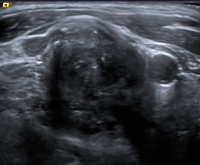

Abbildung 1: Normalbefund zervikal. Diesen kennzeichnet eine scharfe Begrenzung, ein echoreicher Hilus, eine gleichmäßige Breite des Kortex, eine reguläre Größe und ovale Form.